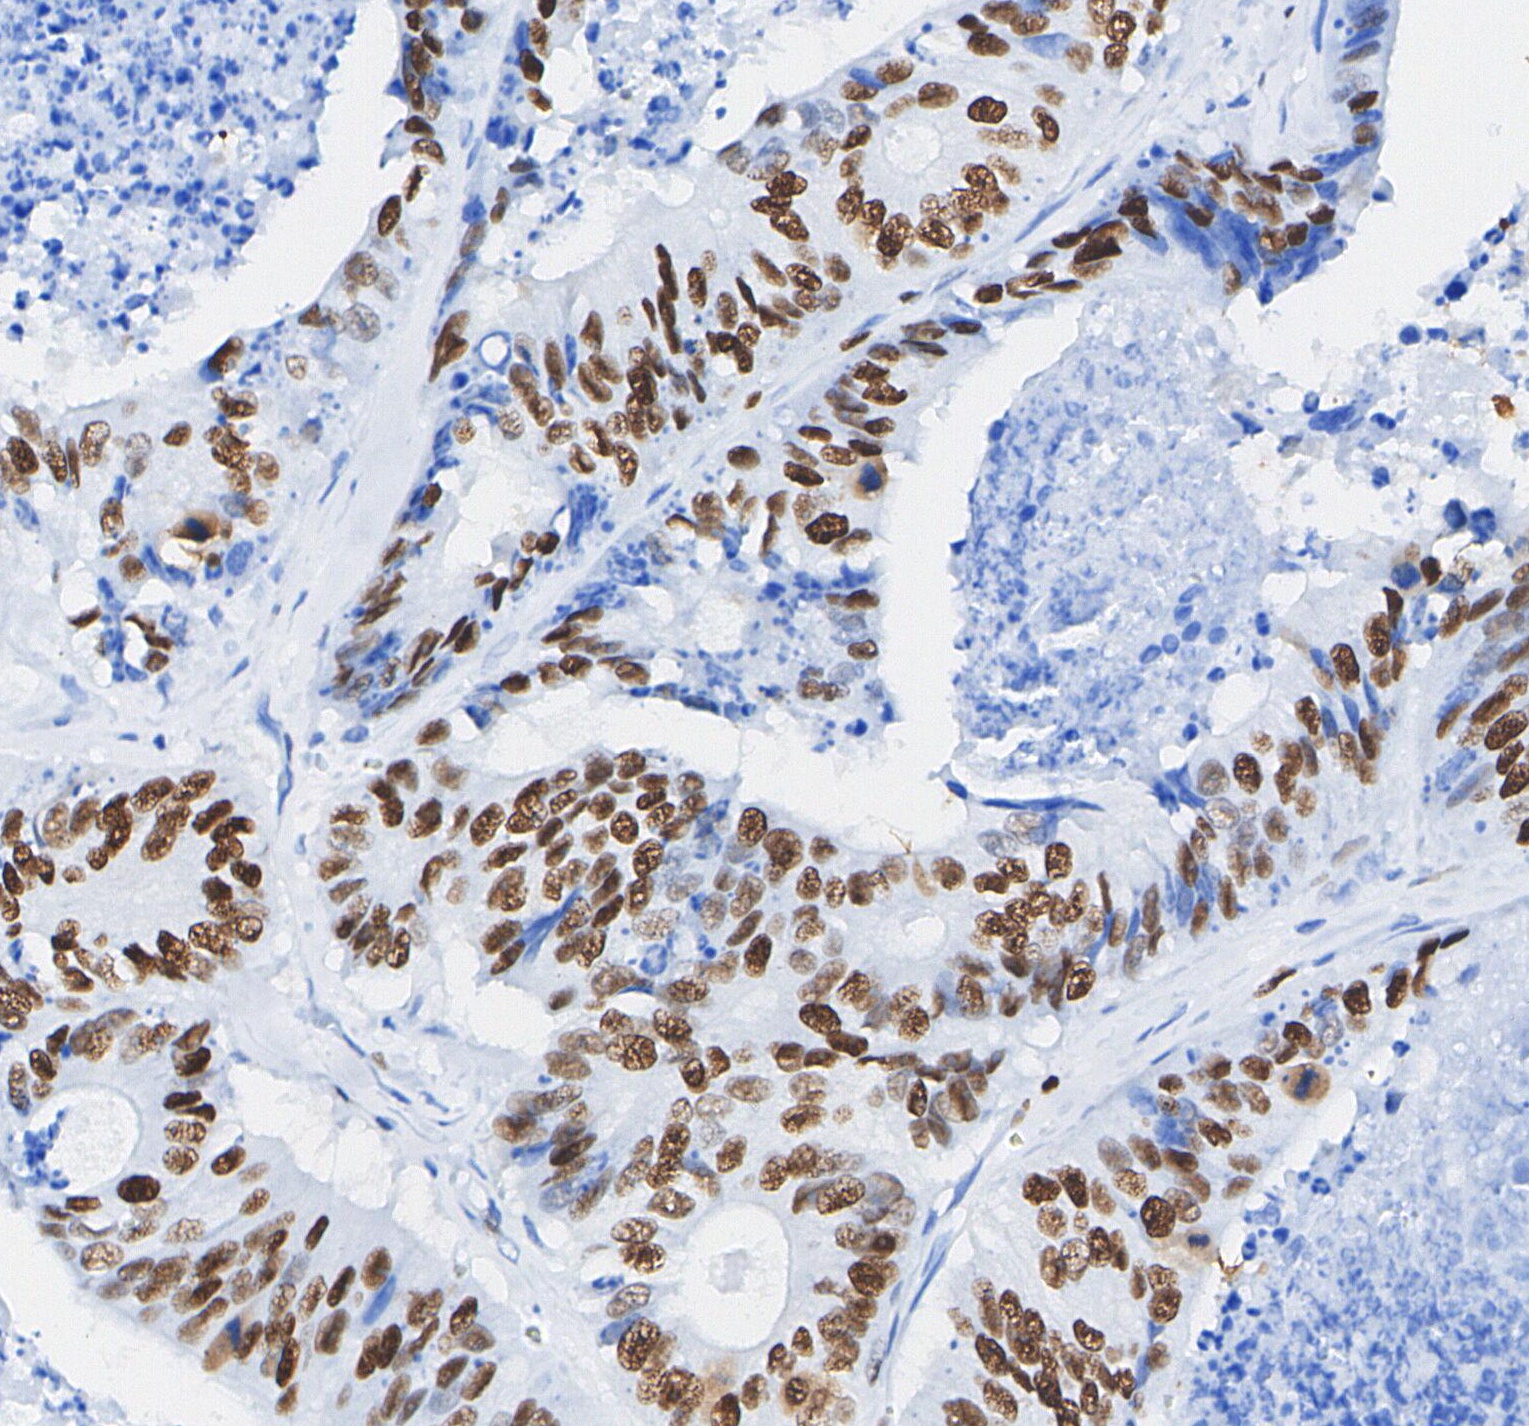

• Immunohistochemical analysis of formalin fixed paraffin embedded human Colorectal cancer tissue with F0136 at 1/100 dilution.

1:100